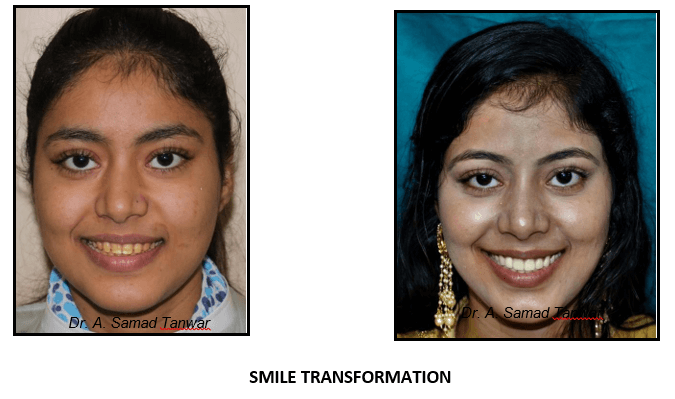

Rehabilitation of a Young Patient with Hypoplastic Dentition –A Case Report.

Patient reported to the Department of Prosthodontics with a chief complaint of discoloured teeth

The intraoral photographs of the patient reveals yellowish discolouration of teeth with generalized

On thorough clinical examination it was found that patient has enamel hypoplasia.

Restoration of aesthetic and function by using blend of conventional and minimally invasive

Besides having the best technical knowledge and experience, Dr. Samad is known to have great interpersonal skills. He believes in building patients’ confidence by giving them their perfect smile.